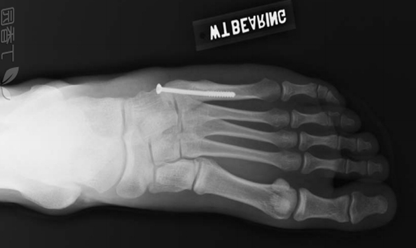

跖骨骨折作为足部最常见的损伤之一,其中约有70%会涉及到第五跖骨,而第五跖骨骨折端的病例中约80%发生于基底部。

• Ⅰ区:骨折是跖骨粗隆部撕脱骨折,发生率最高;

第五跖骨Ⅰ区骨折分型:Ekrol等把第五跖骨Ⅰ区骨折按部位从近而远又分为3个类型:(如图所示)

• 1型:是粗隆尖部骨折;

• 2型:是从第五跖骨基底到第五跖骨-骰骨关节面的斜形骨折;

• 3型:是通到第四跖骨关节面的横行骨折。